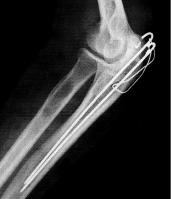

WARNING — This post includes an x-ray of some new hardware that some may find disturbing.

Just a quick note that I had surgery on my elbow on Tuesday as planned — two TI pins plus some extra wire so the bone will heal properly. Back home yesterday, in time to watch #1 son’s high school graduation and make a short visit back to work today, to be followed with a longer day tomorrow.

The arm is in a half cast for the time being, but in a week I should be able to start to move it and do some rehab exercises. The ribs also feel as if they are healing, but I probably won’t be on a bicycle again until after a trip that is scheduled in late June, and I am still scratching my head about what I can do to reduce the risk of another injury, since I don’t enjoy the whole hospital experience. I will need another visit anyway in 6-12 months to have the hardware removed.